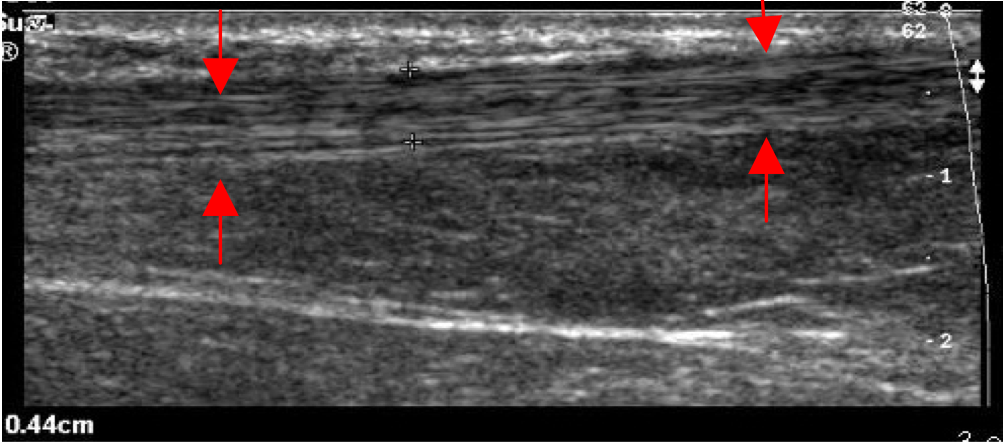

6 7 3 Partial Achilles Tendon Ruptures Ultrasound Cases